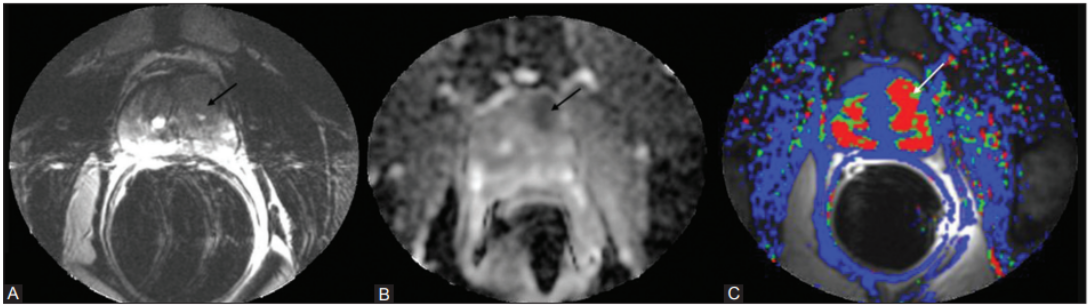

Most clinically important prostate tumours are adenocarcinomas. On MRI, they tend to be dark on T2, show restricted diffusion (low ADC), and often enhance early with contrast, but appearances vary by zone, grade, and size26.

Most prostate cancers are acinar adenocarcinomas arising in the peripheral zone; on mpMRI, these usually appear as focal, round or oval low-signal areas on T2-weighted images, with marked diffusion restriction and corresponding low ADC values27.

Transition zone cancers are also usually adenocarcinomas but are embedded within BPH Anodules, so they often look like ill-defined, lenticular, T2-dark areas with obscured margins, requiring closer attention to diffusion and enhancement patterns to separate them from benign nodules29.

Clinically significant cancers (higher grade, larger volume) tend to show more pronounced diffusion restriction, with very low ADC and very bright high-b-value DWI signal, and more conspicuous, early contrast uptake on dynamic imaging30. These lesions are more likely to be scored PI-RADS 4-5 and correlate with higher Gleason/ISUP grades on biopsy.

mpMRI combines at least three components: high-resolution T2-weighted images for anatomy, DWI/ADC for cell density, and dynamic contrast-enhanced (DCE) imaging for vascularity32. This protocol is still the reference standard in many centres because it improves confidence in calling a lesion benign vs clinically significant, and it underpins PI-RADS.